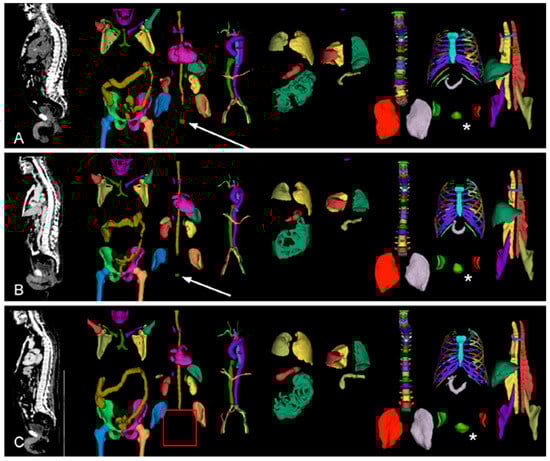

2.3.2. Model B: Cropped Around the Prostate

The data include the whole body, while the specific question (local recurrence) can be answered by focusing on the area around the prostate (region). To automatically crop image volumes around the prostate, the location of the prostate was determined by TotalSegmentator (version 2.1.0, [20]). This worked in most cases, even for patients after radical prostatectomy. In the remaining cases, the position of the urinary bladder was used as a proxy (Figure 2). Images were cropped to a 20 cm × 20 cm × 20 cm cube around the centroid of the prostate (or urinary bladder) in patient coordinates and re-scaled to 70 × 70 × 70 voxels. Variants with stronger cropping were explored (Appendix A).

Appendix A.2.3. Cropping of NIfTIs Using TotalSegmentator

In order to limit the image area of the NIfTIs to the area relevant to the research question, inner body regions were first segmented using the TotalSegmentator [20]. An overview of the regions segmented by the TotalSegmentator in three different patients can be seen in Figure 2 of the main text.

Because there were 39 patients in whom no prostate (region) could be found, the cropping of the NIfTIs had to be performed in two steps. First, the NIfTIs for the cases in which the prostate (region) was detected were cropped based on the prostate. For this the segmented prostate was used as the center of the image and the new image area was defined as a cube around it. Second, in cases where no prostate (region) could be detected, the urinary bladder (UB) (Figure 2 in the main text, *) was chosen as the center of the new image area, as it is in close proximity to the prostate.